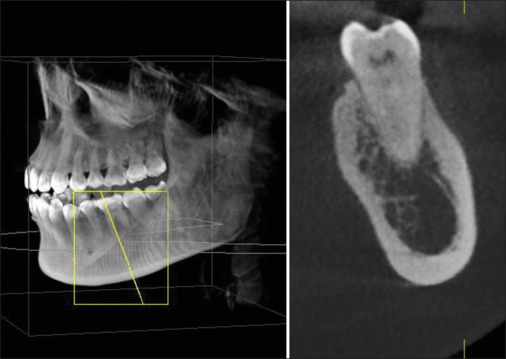

Context: The mandibular canal (MC) is an essential landmark that should be considered before any surgeries. Therefore, accurately assessing the location and characteristics of the MC in cone beam computed tomography (CBCT) imaging is very important.

Methods and material: This was a retrospective study of 112 CBCT images of Vietnamese patients aged 18 to 69 years, taken for clinical indications between 2018 and 2023. The evaluation was carried out by comparing and arranging the anatomical structures of different planes in three-dimensional space to assess and measure relevant dimensions.

Results: The average diameter of the MC from the apex of the second premolar to the distal apex of the second molar, if there were no missing teeth in this segment, was 2.58 ± 0.52 mm (right) and 2.55 ± 0.54 mm (left). If there were a missing tooth in this segment, the measurements were 2.51 ± 0.79 mm (right) and 2.47 ± 0.45 mm (left). The difference between the two sides regarding the presence or absence of a missing tooth was not statistically significant.

Conclusions: The precise localization of the MC related to the tooth apex and the diameter of the MC can vary in each person. CBCT indications should be considered when establishing treatment planning to avoid damaging the inferior alveolar nerve in the MC.